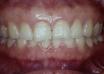

case dot 改善後牙錯咬